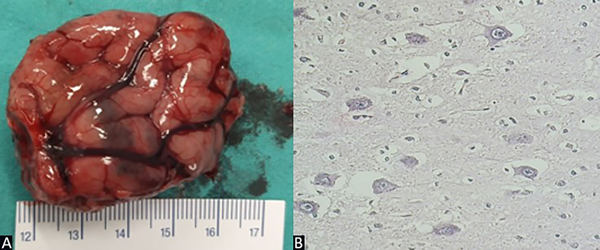

El informe anatomopatológico arrojó el resultado de displasia cortical focal tipo IIb de Taylor (Figura 5).

Figura 5. Caso 1. A) Exéresis de lesión de 4.5 cm de largo. B) Preparado de anatomía patológica: alteración de la laminación cortical, neuronas dismórficas y gigantes, células en balón, núcleos grandes y múltiples.